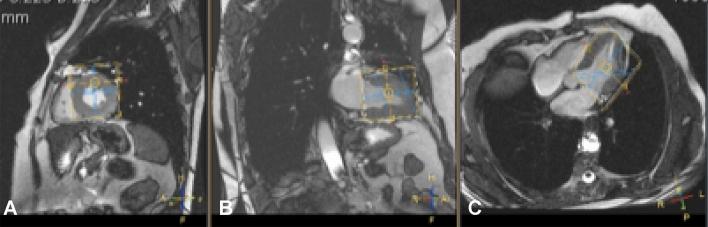

Cardiac energy status, measured as phosphocreatine (PCr)/adenosine triphosphate (ATP) ratio with 31P-Magnetic Resonance Spectroscopy (31P-MRS) in vivo, is a prognostic factor in heart failure and is lowered in cardiometabolic disease. It has been suggested that, as oxidative phosphorylation is the major contributor to ATP synthesis, PCr/ATP ratio might be a reflection of cardiac mitochondrial function. The objective of the study was to investigate whether PCr/ATP ratios can be used as in vivo marker for cardiac mitochondrial function. We enrolled thirty-eight patients scheduled for open-heart surgery in this study. Cardiac 31P-MRS was performed before surgery. Tissue from the right atrial appendage was obtained during surgery for high-resolution respirometry for the assessment of mitochondrial function. There was no correlation between the PCr/ATP ratio and ADP-stimulated respiration rates (octanoylcarnitine R < 0.005, p = 0.74; pyruvate R < 0.025, p = 0.41) nor with maximally uncoupled respiration (octanoylcarnitine R = 0.005, p = 0.71; pyruvate R = 0.040, p = 0.26). PCr/ATP ratio did correlate with indexed LV end systolic mass. As no direct correlation between cardiac energy status (PCr/ATP) and mitochondrial function in the heart was found, the study suggests that mitochondrial function might not the only determinant of cardiac energy status. Interpretation should be done in the right context in cardiac metabolic studies.

心脏能量状态,通过 31P 磁共振波谱(31P-MRS)活体测量磷酸肌酸(PCr)/三磷酸腺苷(ATP)比值来评估,是心力衰竭的预后因素,在心代谢疾病中降低。有人提出,由于氧化磷酸化是 ATP 合成的主要贡献者,因此 PCr/ATP 比值可能反映心脏线粒体功能。本研究旨在探讨 PCr/ATP 比值是否可作为心脏线粒体功能的活体标志物。我们招募了 38 名计划接受心脏直视手术的患者参与这项研究。手术前进行心脏 31P-MRS 检查。在手术期间,从右心房附件获取组织,用于高分辨率呼吸测定以评估线粒体功能。PCr/ATP 比值与 ADP 刺激呼吸率之间没有相关性(辛酰肉碱 R < 0.005,p = 0.74;丙酮酸 R < 0.025,p = 0.41),也与最大解偶联呼吸率没有相关性(辛酰肉碱 R = 0.005,p = 0.71;丙酮酸 R = 0.040,p = 0.26)。PCr/ATP 比值与左心室收缩末期质量指数相关。由于心脏能量状态(PCr/ATP)与心脏线粒体功能之间没有直接相关性,因此研究表明,线粒体功能可能不是心脏能量状态的唯一决定因素。在心脏代谢研究中,应在正确的背景下进行解释。